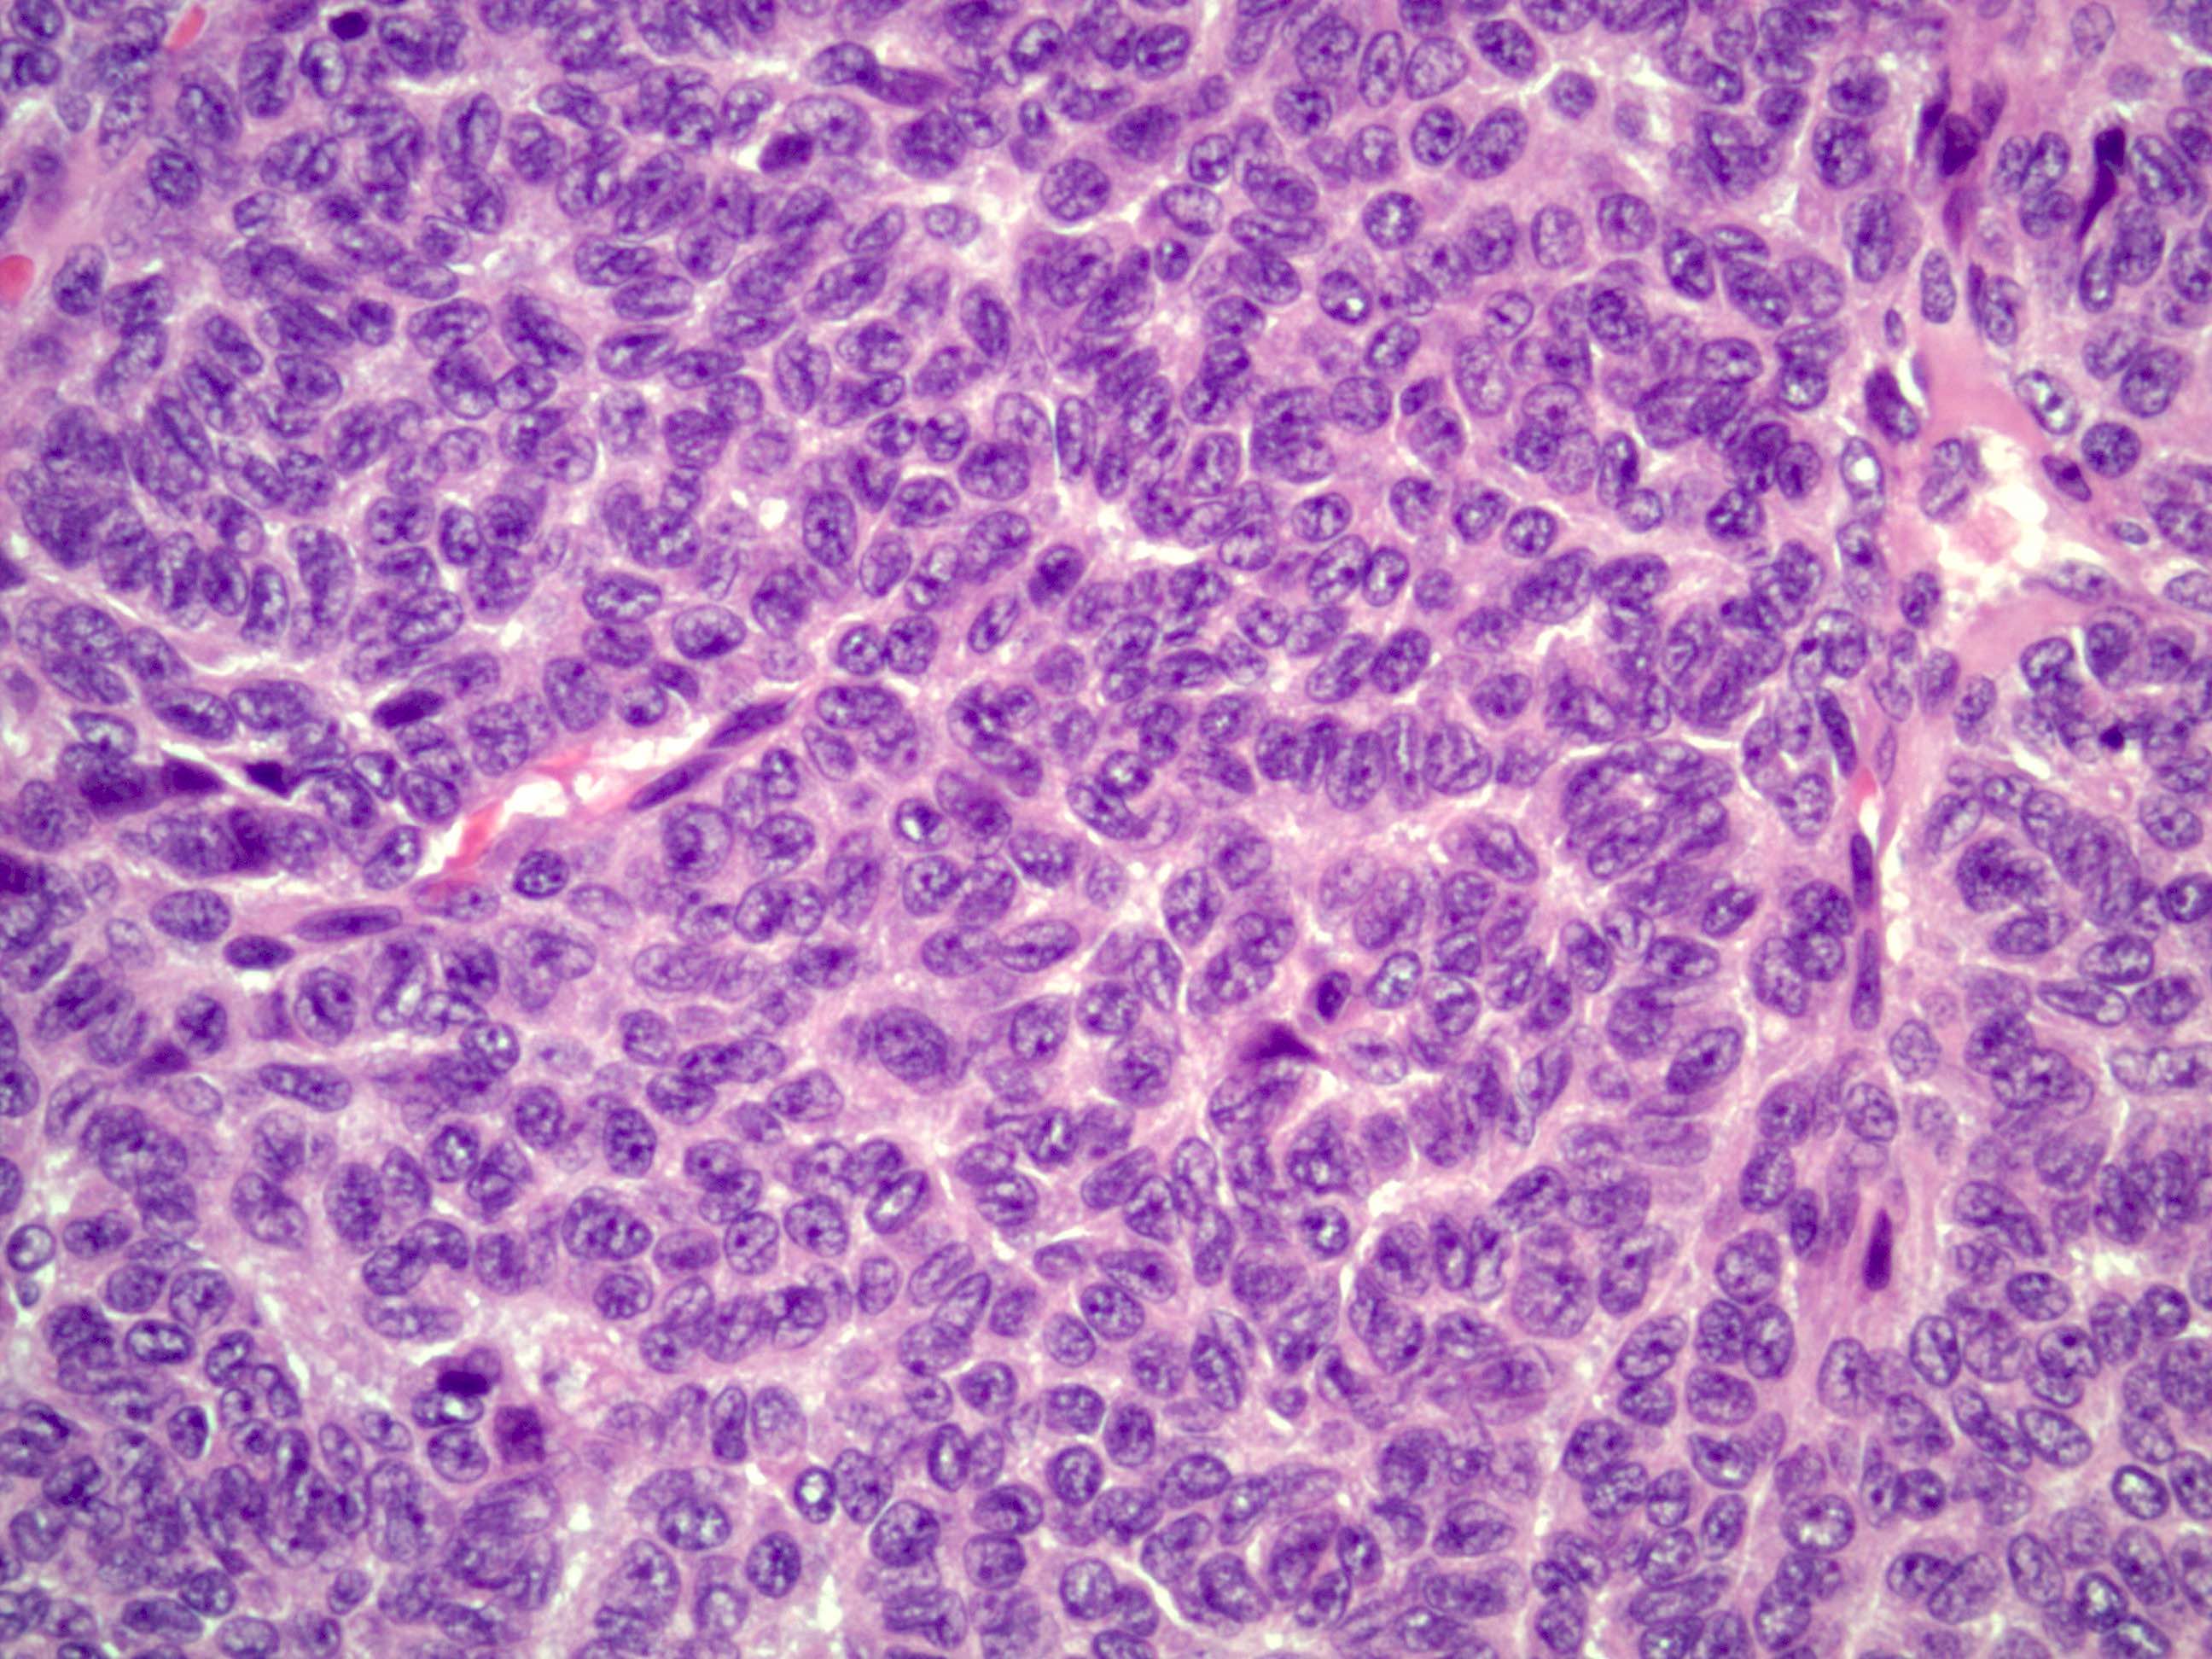

- Small, bland, cuboidal to polygonal cells with scant cytoplasm and pale, uniform angulated and usually grooved nuclei (coffee bean)

- Various patterns, including diffuse (the most common), trabecular and corded, insular, microfollicular (resembling Call-Exner bodies of the Graafian follicles: small follicle-like structures filled with eosinophilic material) and macrofollicular (the least common)

- Usually a mixed growth pattern is seen

- Mitotic activity is usually not brisk (< 3/10 high power fields)

Microscopic (histologic) images

Contributed by Shabnam Zarei, M.D. and Sharon Bihlmeyer, M.D.

AFIP images